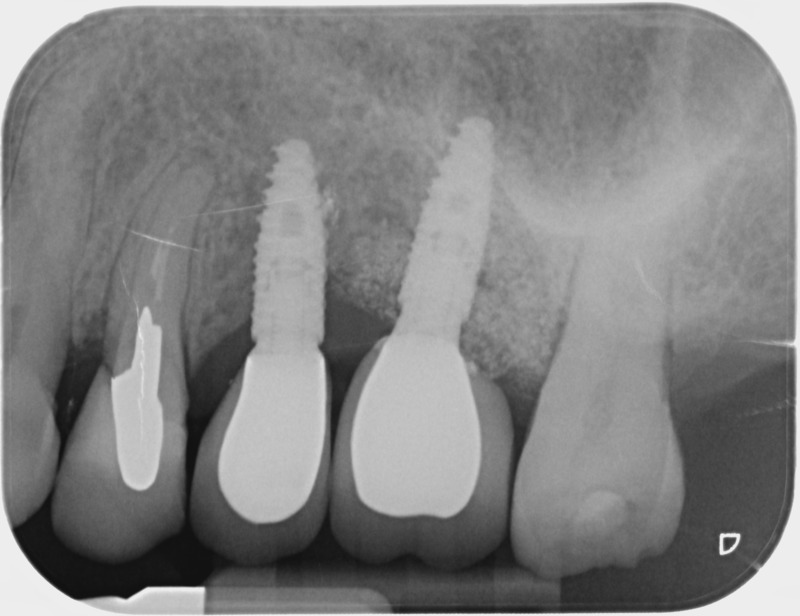

• Couronnes sur implants : Lorsqu’un implant est posé en remplacement des racines d’une dent, il est conçu pour recevoir d’abord un pilier vissé puis une couronne céramique. Le couple couronne - implant se substitue à la dent manquante pour en assurer les mêmes fonctions. Nous pouvons également adapter un bridge sur plusieurs implants dans le cas d’un édentement plus important.

Après